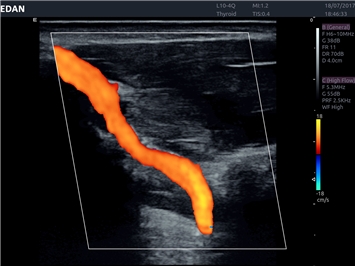

• Повышенная чувствительность при цветовом допплеровском картировании

Цветовой допплер:

Да